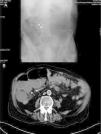

An abdominal X-ray showed small bowel loops with some air-fluid levels (Fig. 1A). His laboratory tests showed leukocytosis with left shift. Given the clinical context of the patient (advanced age and deterioration of general condition), an emergency abdominal computed tomography scan was ordered to complete the diagnosis, in view of the possible need for a surgical procedure. The scan reported distended small bowel loops, but could not identify the cause of obstruction (Fig. 1B).